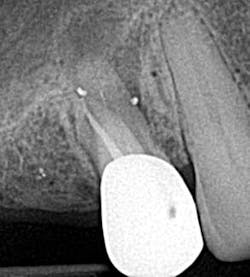

• Access perforations

Drill, poke around. Drill some more. Hmm. I’ve got to be getting close. Let’s just take an x-ray to see how close we are . . . oops! Yeah, that’s happened to me and it’s not how I like to start my root canals (figure 1). The cause of perforations during access is primarily due to lack of attention to the degree of axial inclination and failure to hold the bur parallel to the tooth. (1) Inadequate access can also lead to misdirection and unintended gouging. Signs of perforation include sudden pain, hemorrhaging, burning pain or bad taste during irrigation, periodontal ligament reading from the apex locator, and a radiographically malpositioned file. (1) Prevention includes understanding tooth morphology, accessing without a rubber dam (in instances where angulation, calcified chambers, and misoriented crowns skew tooth alignment), (1) having multiple radiographs to reference, and patience . . . lots and lots of patience, especially when you have small, calcified chambers that want to be eluded.